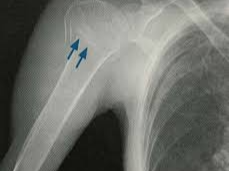

어깨에 골절이 발생하면 일상 전체가 마비되는 기분을 느끼는 것도 무리는 아닙니다. 특히 쇄골, 상완골 근위부, 견갑골 부위에 골절이 생기면 수술이 필요하며, 수술 이후의 재활과 물리치료는 단순히 통증을 없애는 것을 넘어, 관절 가동 범위의 회복과 장기적인 기능 정상화를 위한 핵심 단계입니다. 또한 어깨 골절 수술 이후 본격적으로 시작되는 재활 치료와 도수치료의 현실적인 문제는 ‘비용’과 ‘보험 적용 여부’입니다.